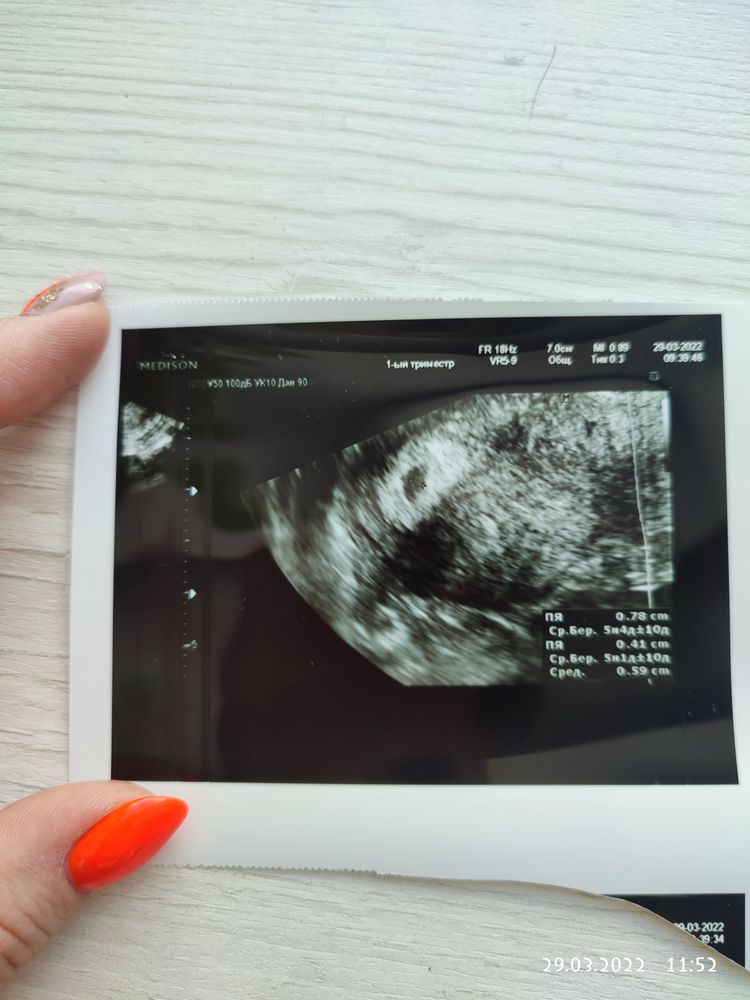

20 ДПП первое УЗИ 🌞🌞🌞

Поздравляю 🙌🙏 у нас на 17 дпп ПЯ в матке 5 мм. И 5-го апреля на втрое узи ☺️Так хочется услышать сердечко 🙏

Карина, про отставание врач ничего не сказала...по размерам ПЯ все соответствует сроку, я вчера пост выкладывала, девочки писали ,что и после 7 недель только эмбриончик показывался, а подружка вчера сказала,что у нее к 8 ближе только увидели, уже на аборт отправляли или чистку...Все индивидуально.Я жду 14 число, настраиваюсь на лучшее, но переживаю.Надеюсь,все же, что в гос клинике не очень аппарат УЗИ, поэтому и не видно...Напишите как у вас пройдет все.Вообще, я нашла табличку среднего размера ПЯ и соответствие сроку, приложу сейчас Изображение Изображение